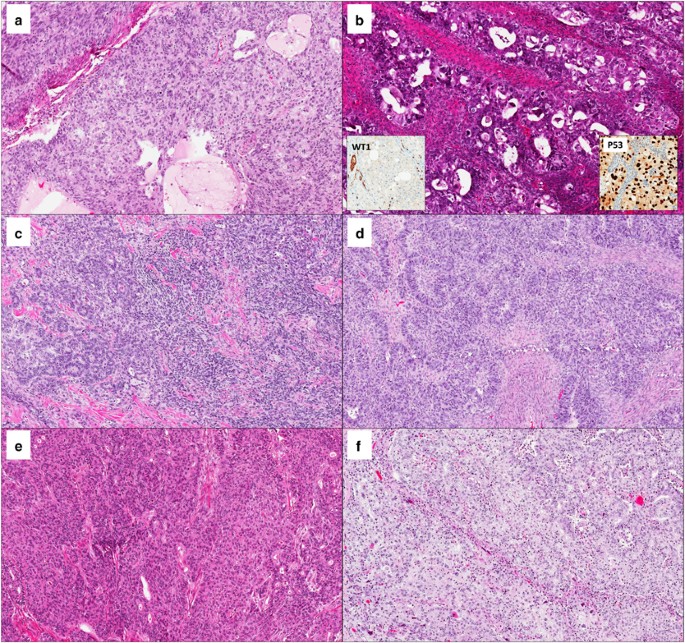

(a, b) Low-grade (a) and high-grade (b) ovarian endometrioid carcinomas, with negative WT1 and abnormal p53 expression (absent in a, overexpressed in b); both patients developed tumor recurrence. (c, d) Low-grade (c) and high-grade (d) ovarian endometrioid carcinomas with negative WT1 and wild-type p53 expression. (e) High-grade ovarian endometrioid carcinoma with MLH1 loss. (f) High-grade ovarian endometrioid carcinoma harboring a pathogenic POLE mutation. Arrows in (a and f) indicate foci of squamous differentiation.

Distribution by FIGO histologic grade was as follows: 33 (46%) grade 1; 24 (33%) grade 2; and 15 (21%) grade 3. All cases had at least one confirmatory endometrioid feature; ovarian endometriosis was identified in 65/72 (90%) cases. Endometrioid glandular morphology was consistently seen in all cases. Non-morular solid growth was present in varying proportions. Predominant transitional-like, papillary or micropapillary growth patterns were not observed in any of the cases included. The morphologic spectrum of ovarian endometrioid carcinoma in our series is depicted in Figures 1 and 2.

High-grade (FIGO 3) ovarian endometrioid carcinomas. (a–c) Tumors with abnormal p53 expression; these tumors are characterized by a predominant solid growth, admixed with endometrioid-type glands and exceeding 50% of the tumor volume; severe nuclear pleomorphism is noted in (a and b); inserts in (b) depict negative WT1 and p53 overexpression. (d, e) Tumors with wild-type p53; predominant non-morular solid growth; tumor in (d) had areas with sex cord appearance. (f) MMR-deficient tumor with glandular and solid architecture.

Misclassification of other types of ovarian carcinoma, especially serous, as endometrioid is documented; in fact, it has been postulated that the majority of high-grade endometrioid carcinomas represent serous carcinomas with variant (solid, endometrioid, and transitional—SET) morphology.23 To rule out mimics of endometrioid morphology, expert pathologist review was carried to confirm an endometrioid phenotype and exclude serous carcinomas with SET morphology. Histopathologic analysis showed a spectrum akin to that observed in endometrial tumors, characterized by endometrioid-type glands with smooth luminal borders and columnar cells. High-grade cases had non-morular solid growth exceeding 50% of the tumor volume; nuclear pleomorphism ranged from mild to severe. Moreover, all carcinomas in our study had at least one confirmatory endometrioid feature as an inclusion criterion (endometriosis, endometrioid adenofibroma background, and/or squamous, mucinous, or secretory metaplasia). In addition, we only included tumors that were negative for WT1 and Napsin-A by immunohistochemistry. WT1-positive ovarian endometrioid carcinomas have a gene expression profile similar to serous carcinomas, and likely represent serous tumors misclassified as or mimicking endometrioid morphology.22, 23 Thus, under current immunohistochemical algorithms ovarian endometrioid carcinoma is defined as hormone receptor-positive, Napsin-A-negative and WT1-negative.19, 20, 24 Some authors have reported WT1 expression in up to 30% of endometrioid carcinomas,25, 26 although misclassification of high-grade serous carcinomas as endometrioid in such studies is probable.22 On the basis of the criteria outlined above, tumor type misclassification in our cohort is considered unlikely.